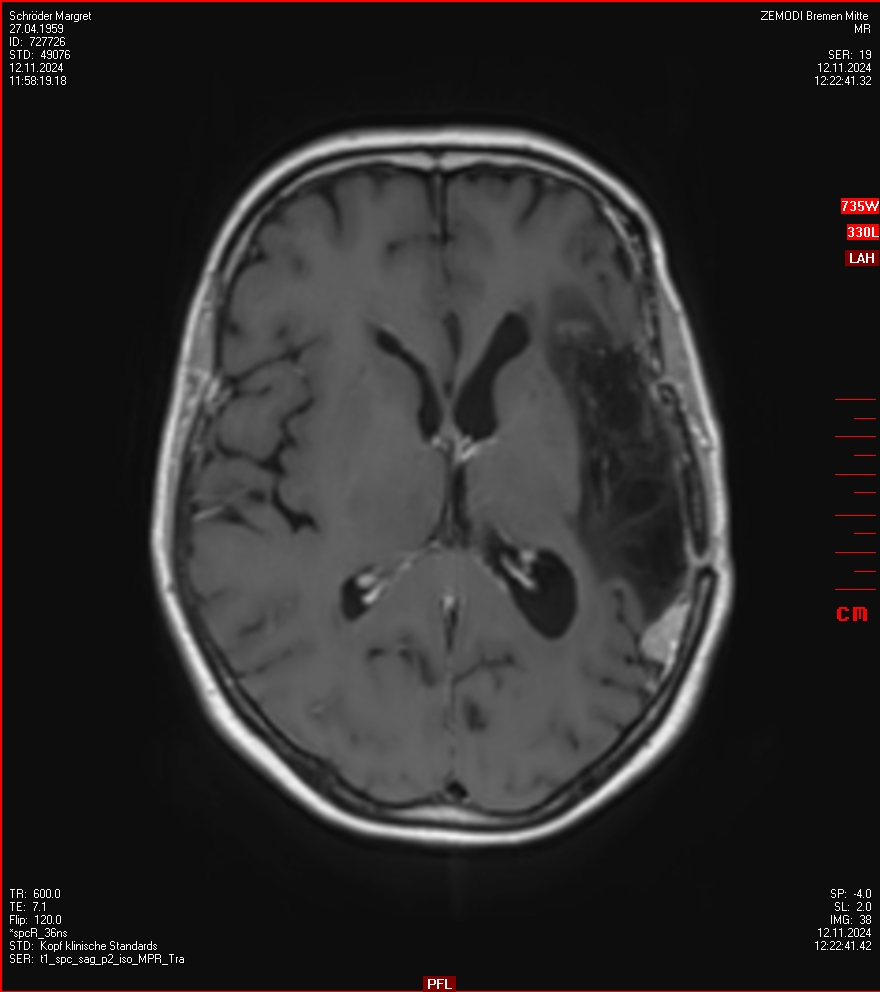

MRT vom 12. November 2024

So nun ein paar neue Bilder aus meinem Kopf. (Durch klicken bekommt man eine größe Ansicht eines Einzelbildes).

Die letzten drei Bilder Zeigen aus meiner Sicht den Tumor, der im Jahr 2021 bestrahlt wurde.

Ich denke, in den letzen 12 Monaten sind da ein paar Rezidive gewachsen,  vor 12 Monaten waren sie auch schon zu erkennen - vorher noch nicht. Nun hoffe ich auf den Rat des Spezialisten. Hoffendlich kann man etwas machen.